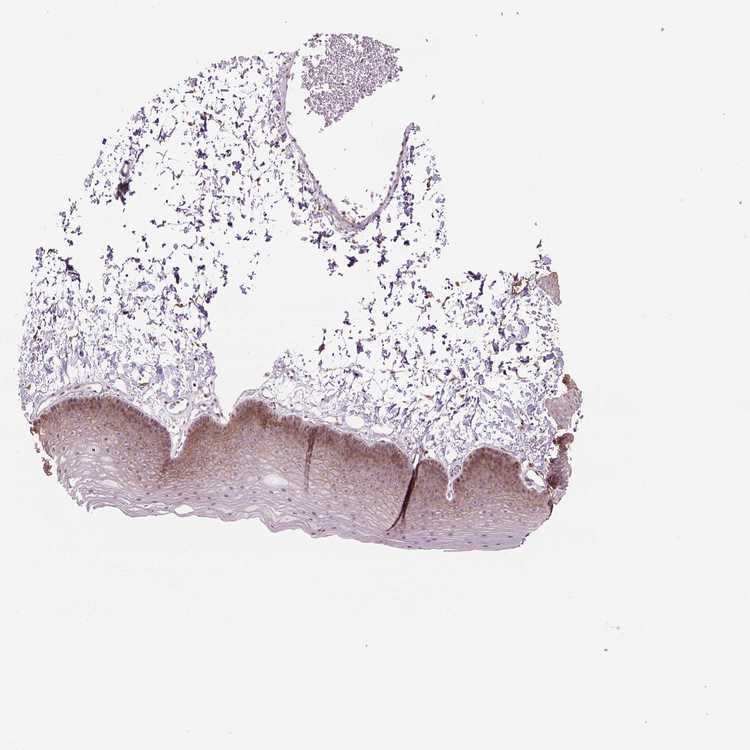

SKIN 2 - Antibody stainingi

Antibody staining in the annotated cell types in the current human tissue is reported as not detected, low, medium, or high, based on conventional immunohistochemistry profiling in selected tissues. This score is based on the combination of the staining intensity and fraction of stained cells.

Each image is clickable and will lead to virtual microscopy that enables deeper exploration of all samples and also displays staining intensity scores, fraction scores and subcellular localization as well as patient and tissue information for each sample.

Antibody HPA067595Antibody HPA069443Antibody CAB022062

Arrector pili muscle cells Not detected--

Cells in basal layer Medium--

Cells in corneal layer Not detected--

Cells in granular layer Not detected--

Cells in spinous layer Medium--

Endothelial cells Medium--

Epidermal cells -LowMedium

Extracellular matrix Not detected--

Fibrohistiocytic cells High--

Langerhans cells Not detected--

Lymphocytes Not detected--

Melanocytes Medium--

Vascular mural cells Not detected--